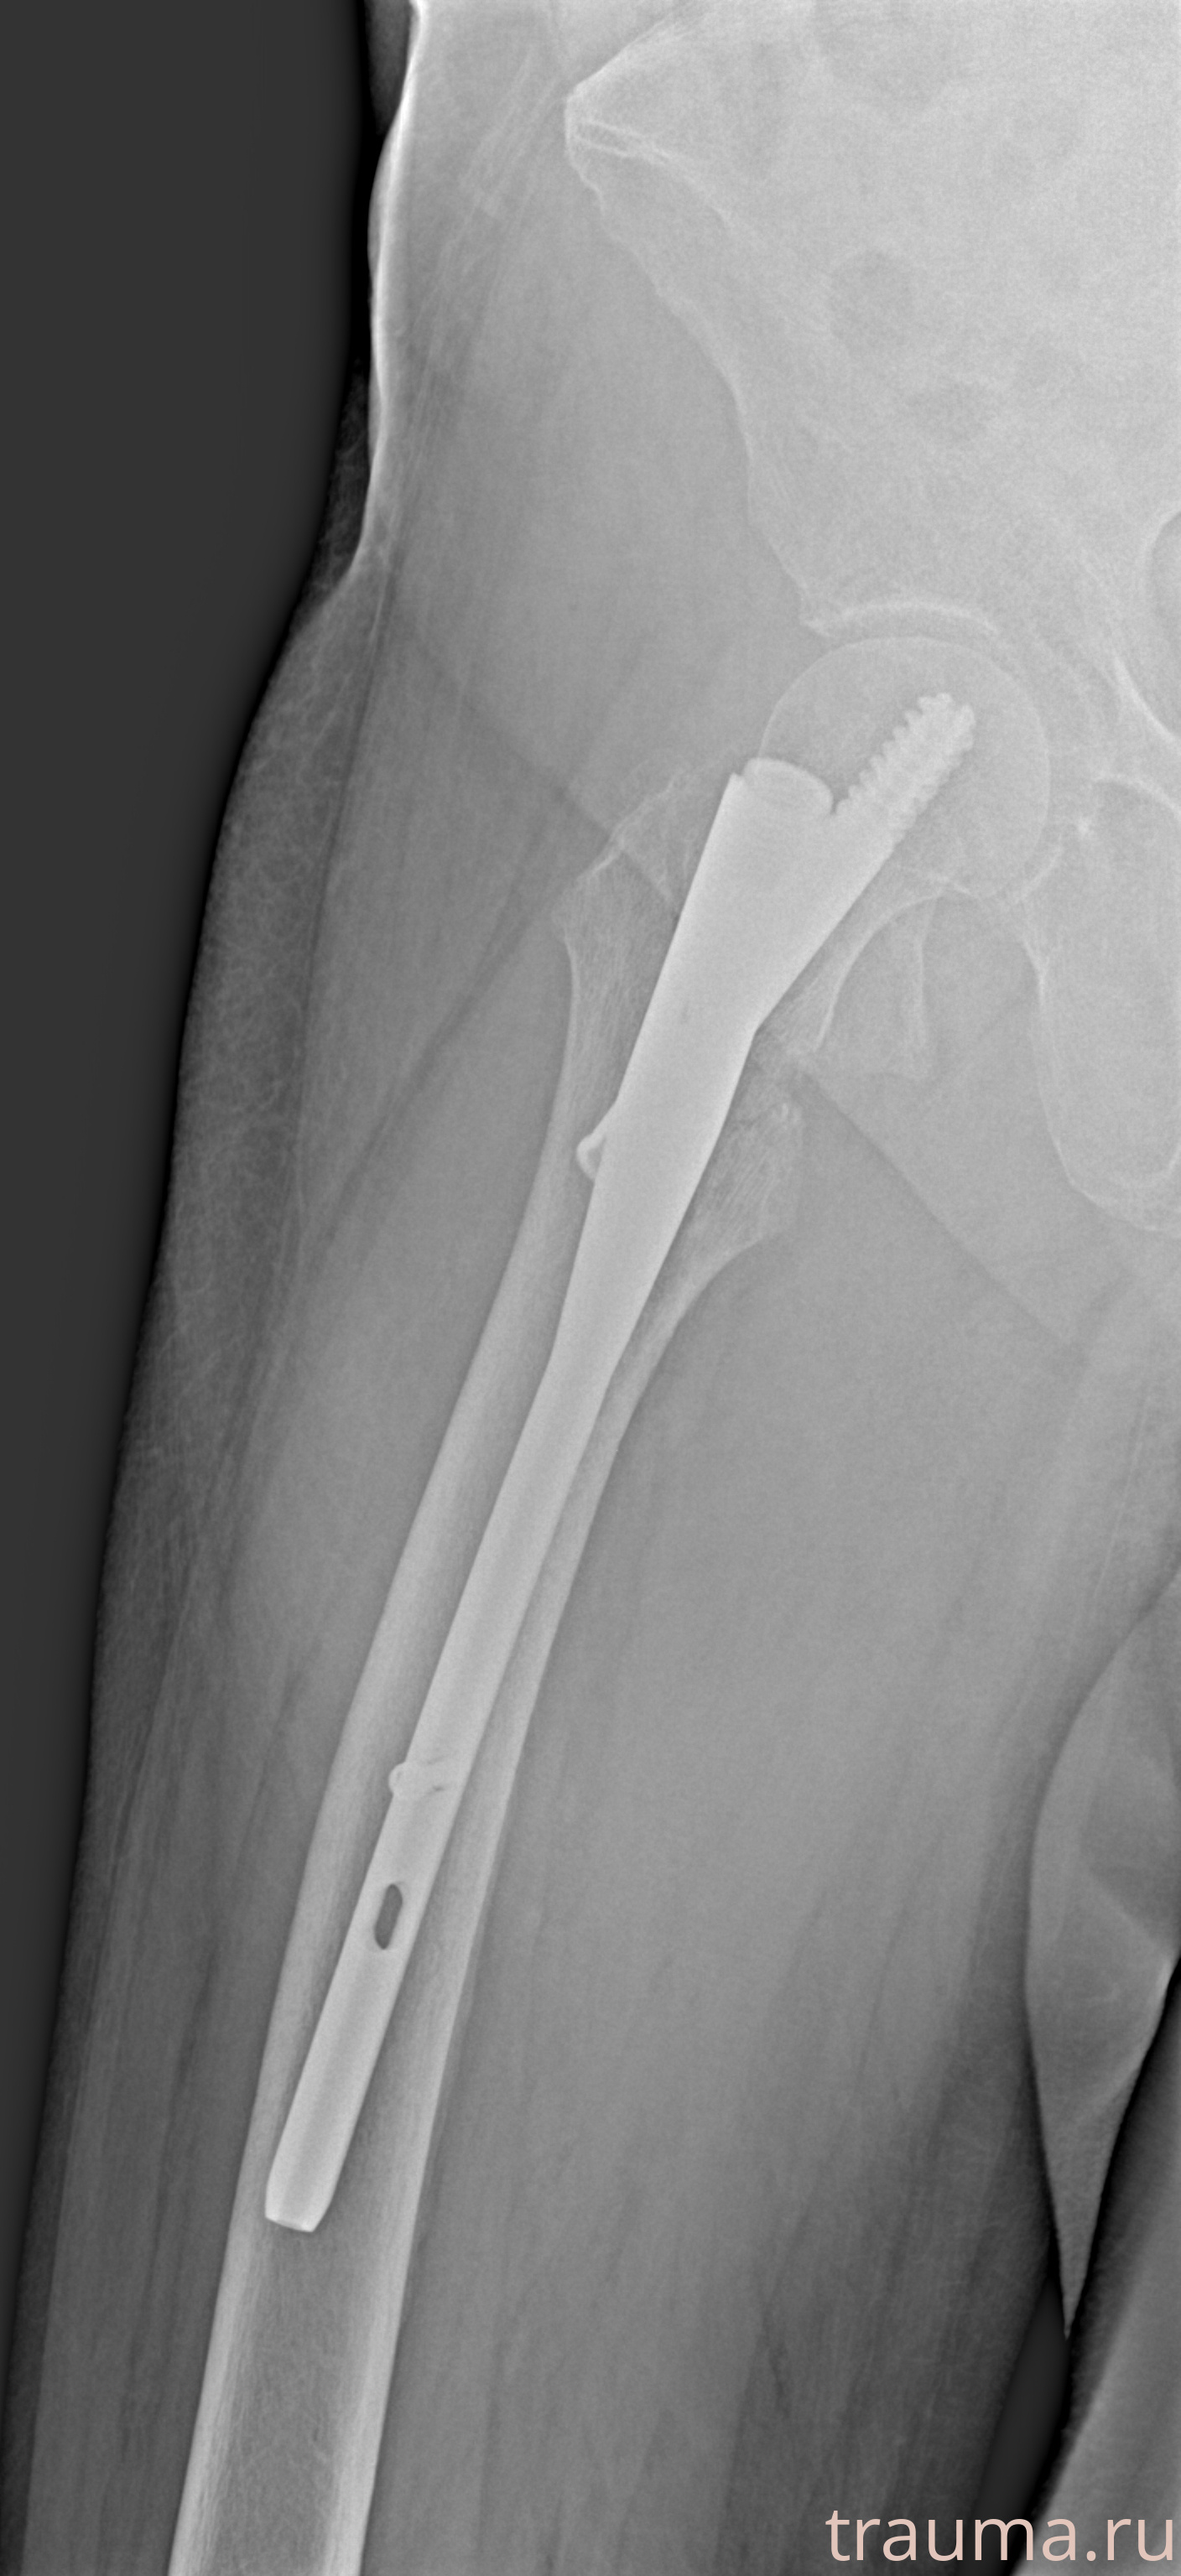

Рентгенограммы

Рентген на дому: по вашему адресу приезжает врач-рентгенолог, травматолог-ортопед с мобильным рентгеновским аппаратом, проводит диагностику травмы или заболевания, делает необходимые рентгенограммы, дает рекомендации по дальнейшему лечению. Получить качественные снимки в домашних условиях возможно благодаря уникальной методике, разработанной МосРентген Центром для института  Склифосовского